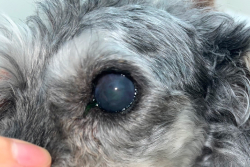

Before:潰瘍部分に染色液がのりブルーライトを当てると光ります

After:点眼開始1週間後、染色範囲が狭まりました

目が開きづらそう、目を気にしている、瞬膜が出ている

フルオレセイン角膜染色を実施し角膜潰瘍あり、結膜細胞診で核内封入体を認めヘルペスウイルス感染症の関与も示唆されました。角膜障害治療薬の点眼薬と抗ヘルペスウイルス薬の内服で治療を開始し、徐々に角膜潰瘍の治癒を認めました。ストレスが発症に関与するので出来る限り負担のないように注意しました。

角膜潰瘍は角膜に傷がつき痛みを伴う疾患です。原因としては外傷、異物、逆さまつげ、ドライアイ、免疫異常、感染(ウイルス、細菌、真菌)などがあります。角膜潰瘍は悪化してしまうと角膜穿孔(目に穴があいてしまう)になることもありますので早期の治療が大切です。特に猫ちゃんではヘルペスウイルスの関与が多いため出来る限りストレスのないような治療をご相談しながら選択できればと思います。点眼薬や軟膏、内服薬など様々な方法をご提供させていただきます。